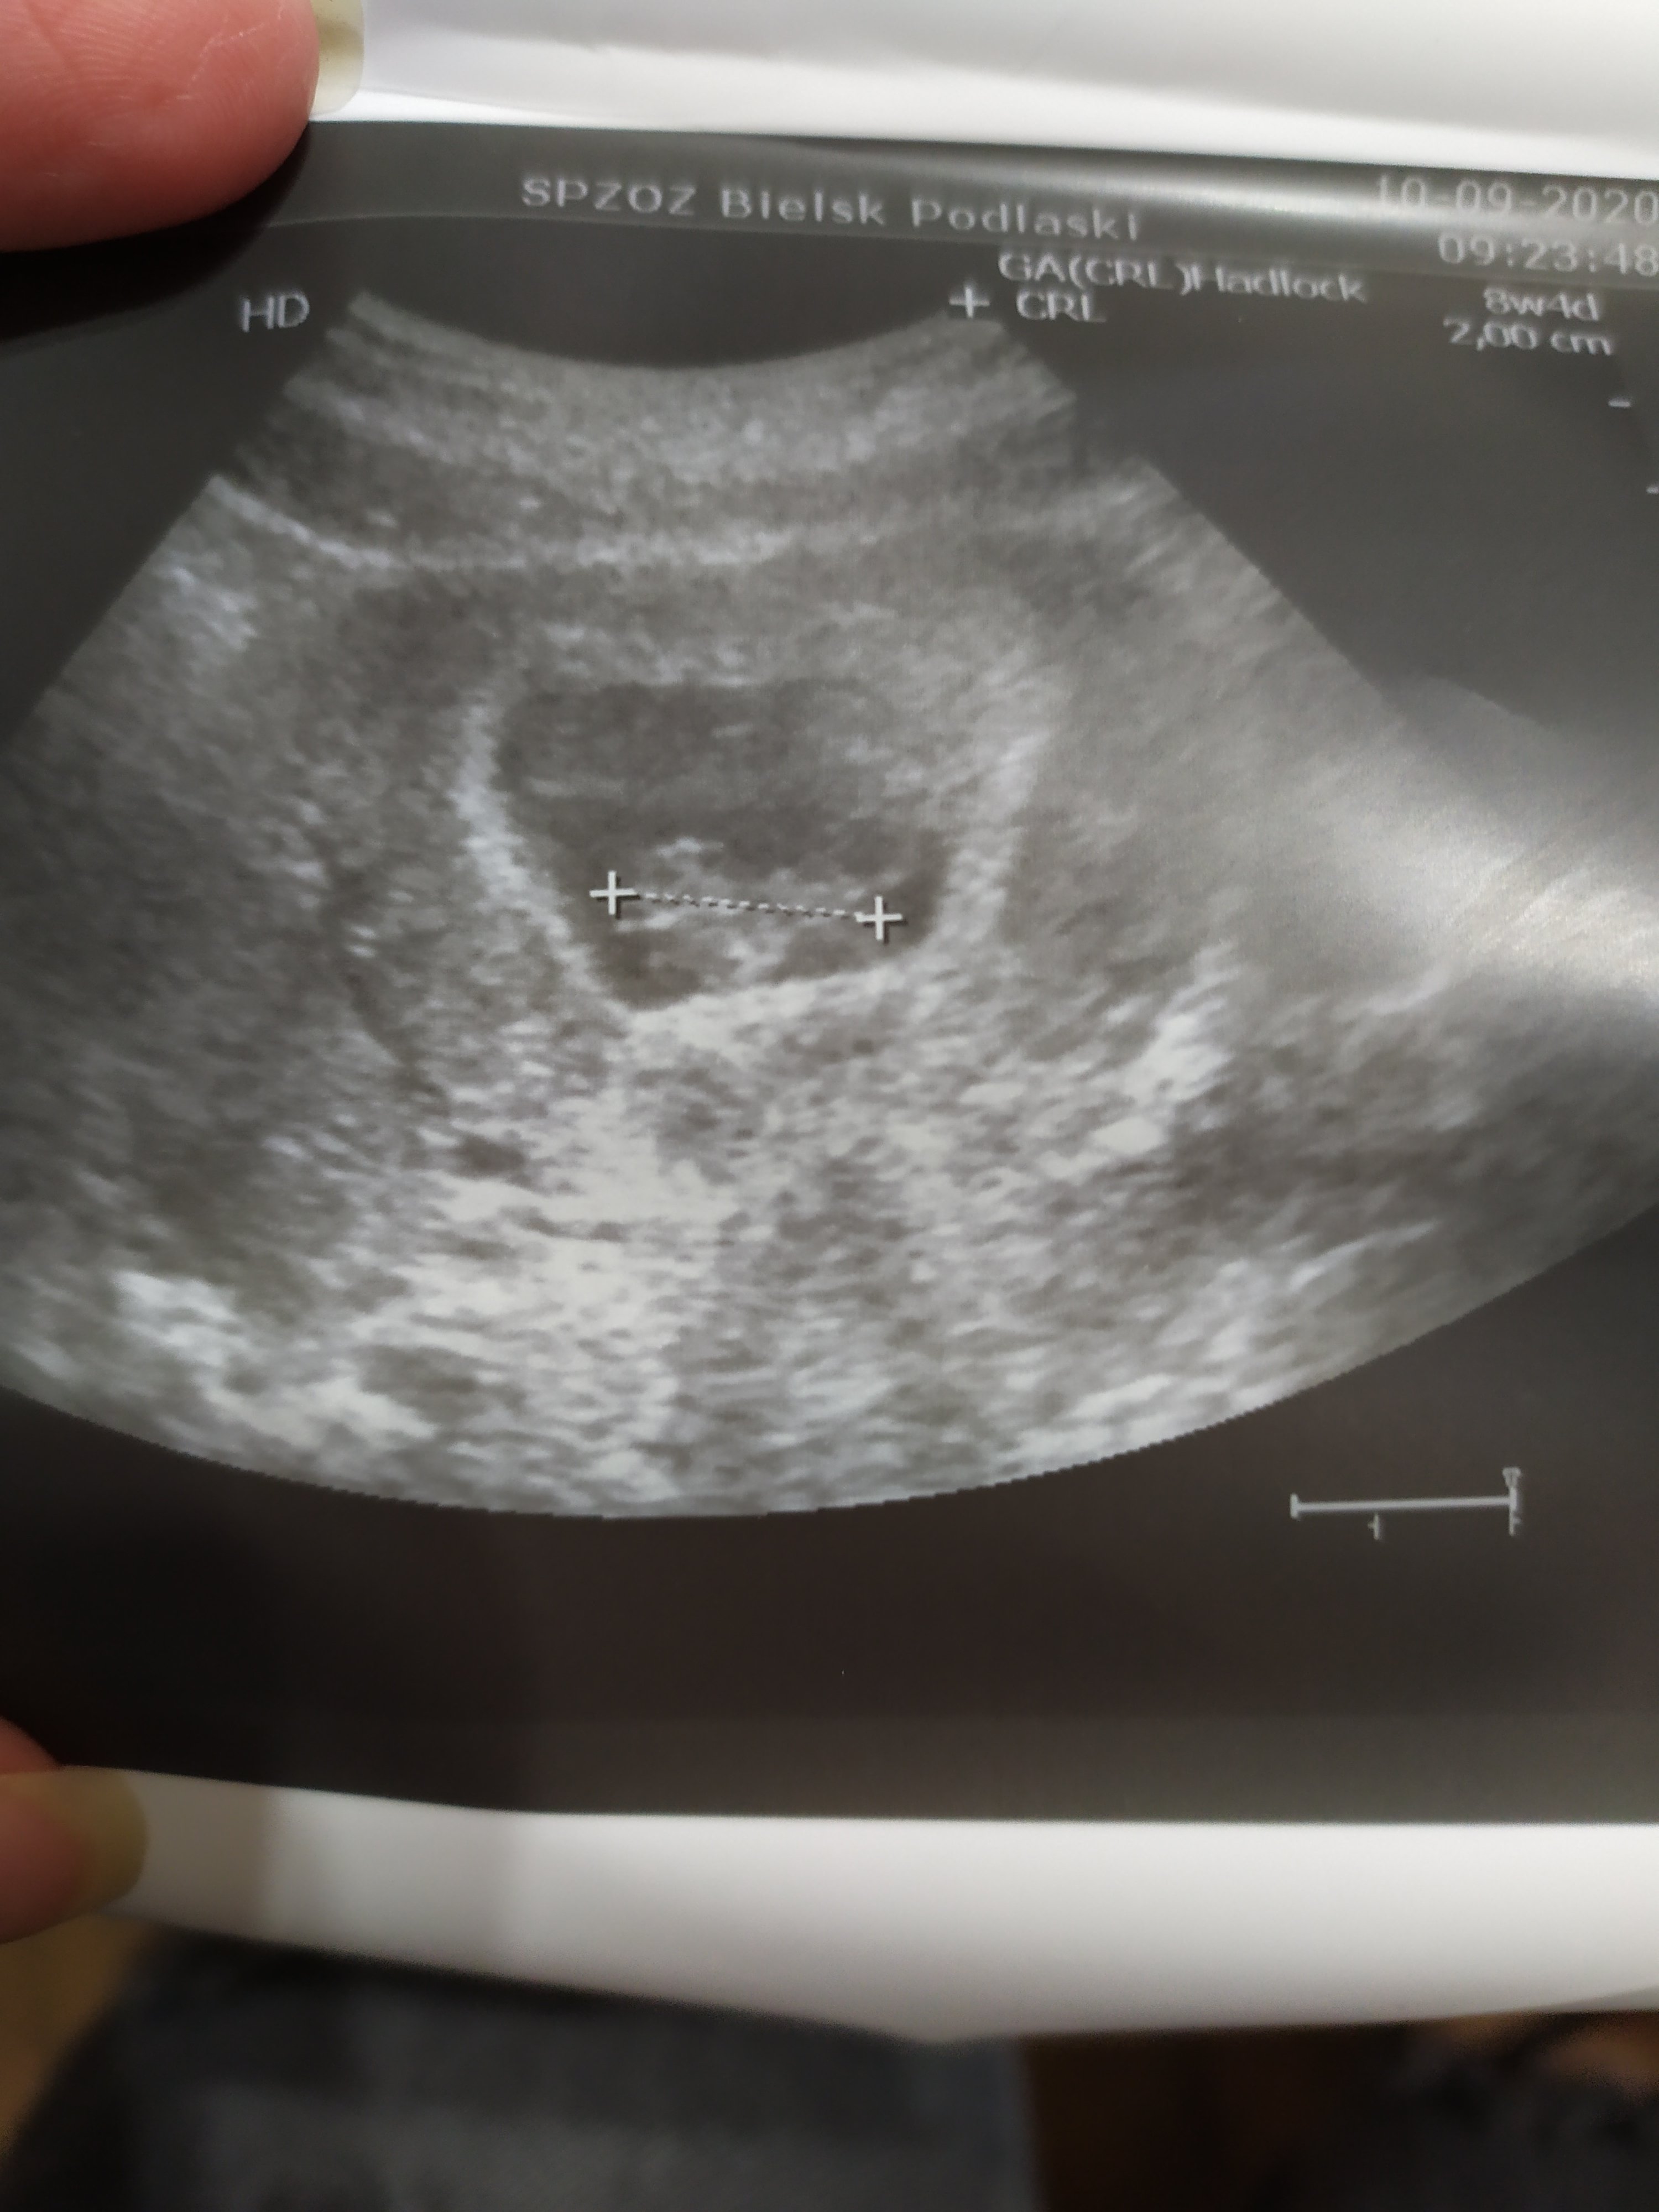

Pieknie!Widziałam jak serducho biłoale to jest efekt